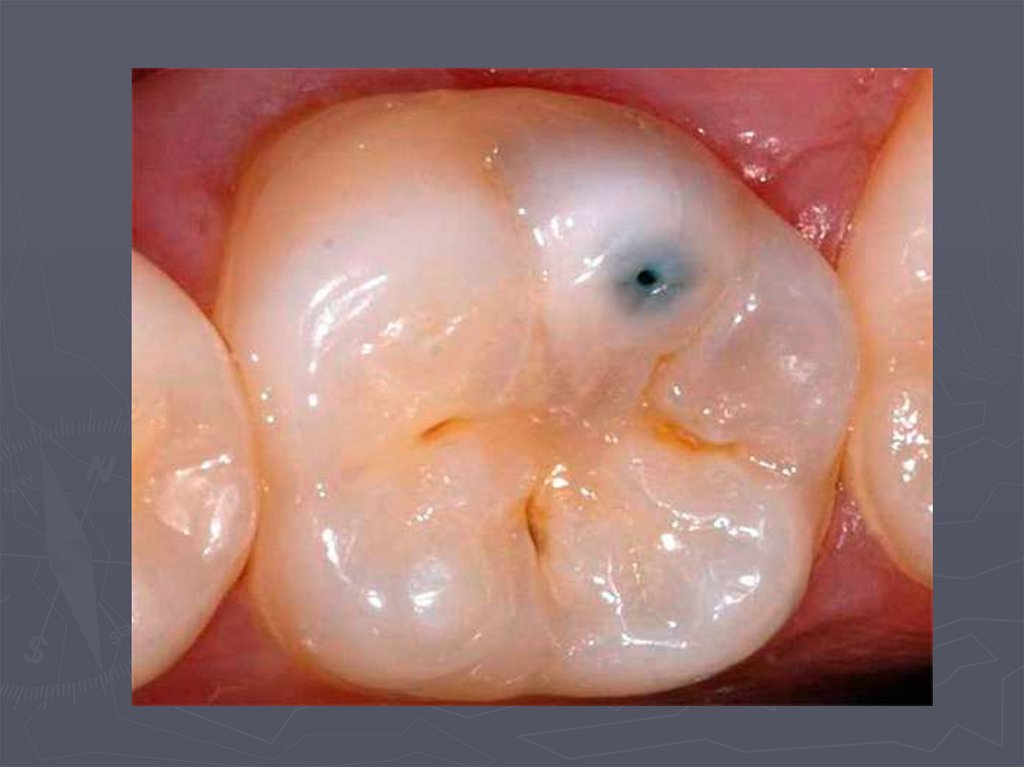

38. КЛИНИЧЕСКАЯ КАРТИНА СРЕДНЕГО КАРИЕСА при декомпенсированной форме:

► при локализации кариозной полости в фиссурах

определяется небольшое входное отверстие;

► при раскрытии обнаруживается кариозная

полость с податливым дентином;

► края кариозной полости нависают;

► эмаль тонкая, хрупкая;

► дентин светлый, влажный, размягченный, легко

удаляется экскаватором;

► зондирование болезненно по

эмалево-дентинному соединению.